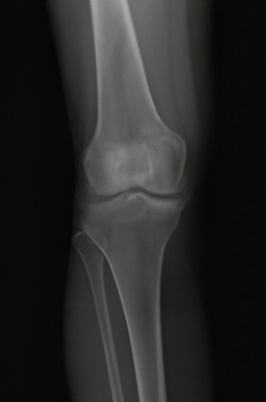

图1 膝骨关节炎x片表现:a早期

膝骨关节炎的早期表现为膝关节疼痛,随着病情进展,会出现疼痛加重并活动受限,关节畸形。患了膝骨关节炎该如何治疗?首先需明确, 治疗的目的主要是2个,即解决疼痛,改善关节功能。 解决了这两个问题,最终就会实现生活质量的提高。那么如何缓解疼痛?怎样改善功能?这是每个膝骨关节炎患者最关心的问题,这需要根据病情的严重程度,采取个体化的治疗手段。患者希望以最小的代价获得最满意的疗效,这也是医生不竭的医术追求。